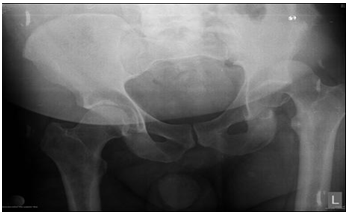

The patient at the age of 34 and 150kg of body weight suffered left hip posterior dislocation with femoral head fracture in car crash accident. The patient had been admitted to hospital after midnight. The mechanism of injury goes as follows: axial force and flexion in the hip caused by impact of the car. The left leg clinically observed is in painful extension, with minimal movement, strong pain and shortened leg. X-rays shows posterior hip joint dislocation and fracture of the femoral head. Closed reduction under anesthesia was unsuccessful. 3D CT reconstruction that had been taken before proceeding to open procedure shows posterior hip dislocation with femoral head fracture above fovea involving weight bearing portion- Pipkin type II fracture dislocation.

Preoperative x-rays, CT scans and 3D CT reconstructions in emergency department are presented as follows (Figure 1-5).

Figure 1 Preoperative X-ray.